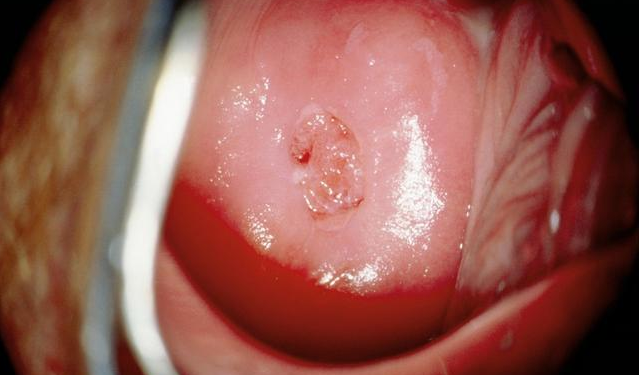

宮頸糜爛其具體表現為宮頸外口處的宮頸陰 道部外呈細顆粒狀的紅色區,宮頸糜爛是一種正常的生理現象,及時治療是不會是不會對受孕造成影響的,但是若伴發炎癥和細菌感染,則有可能刺激陰道分泌增加,不利于精子的活動,也會形象受孕的。

宮頸糜爛有輕度、中度、重度的區別,其中,重度宮頸糜爛不僅容易誘發不孕問題,還容易合并感染HPV病毒感染,誘發宮頸癌的危險。而且容易造成分娩時裂傷的危險,可見,宮頸糜爛是會對分娩早產影響的。

而且,長時間的重度宮頸糜爛會引起宮口松弛問題,這樣就容易造成流產,尤其在懷孕晚期容易發生流產,因此,重度宮頸糜爛對分娩造成的影響很大。